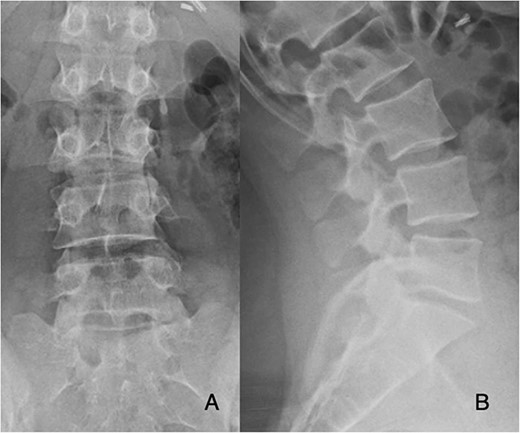

She was followed until 12 weeks post-operatively, with complete resolution of symptoms and did not appear for any appointments past 12 weeks. Radiographs obtained at follow-up demonstrated stable cage and plate placement (Fig. 3).

Post-operative posterior-anterior (A) and lateral (B) films demonstrate ALIF cage and plate placement.